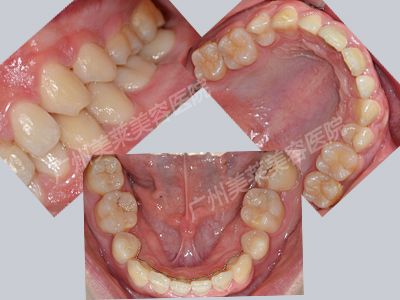

治療方案:美萊活力口腔醫(yī)生唐欽為林偉設(shè)計了一個治療方案,爛壞的牙齒使用美萊生態(tài)仿真烤瓷牙,牙列擁擠、間隙過大問題則利用美萊智能美學正畸,美萊智控矯正…… >>>了解美萊口腔醫(yī)生個性治療方案

治療后林偉牙齒

恢復(fù)時間:一年半

治療后感言:“現(xiàn)在我敢爽朗地笑了,不用擔心難看的牙齒和怕口臭。是個爺們確實不能笑不露齒,有種悶了很久突然得到釋放的感覺,哈哈……”